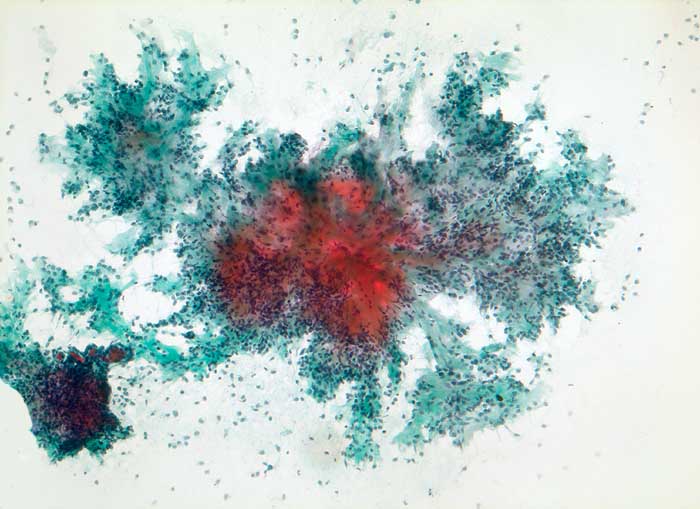

PathoPic – image database / PathoPic ID 5438 - pleomorphes Adenom

pleomorphes Adenom

benigner Tumor

Parotis

Kopf & Hals, Sinnesorgane

Feinnadelpunktion Parotis: Grösserer verzweigter palmwedelförmiger Zellverband mit reichlich Stroma. Spindelförmige und ovale im Stroma eingelagerte Zellen.

Zytologie

100